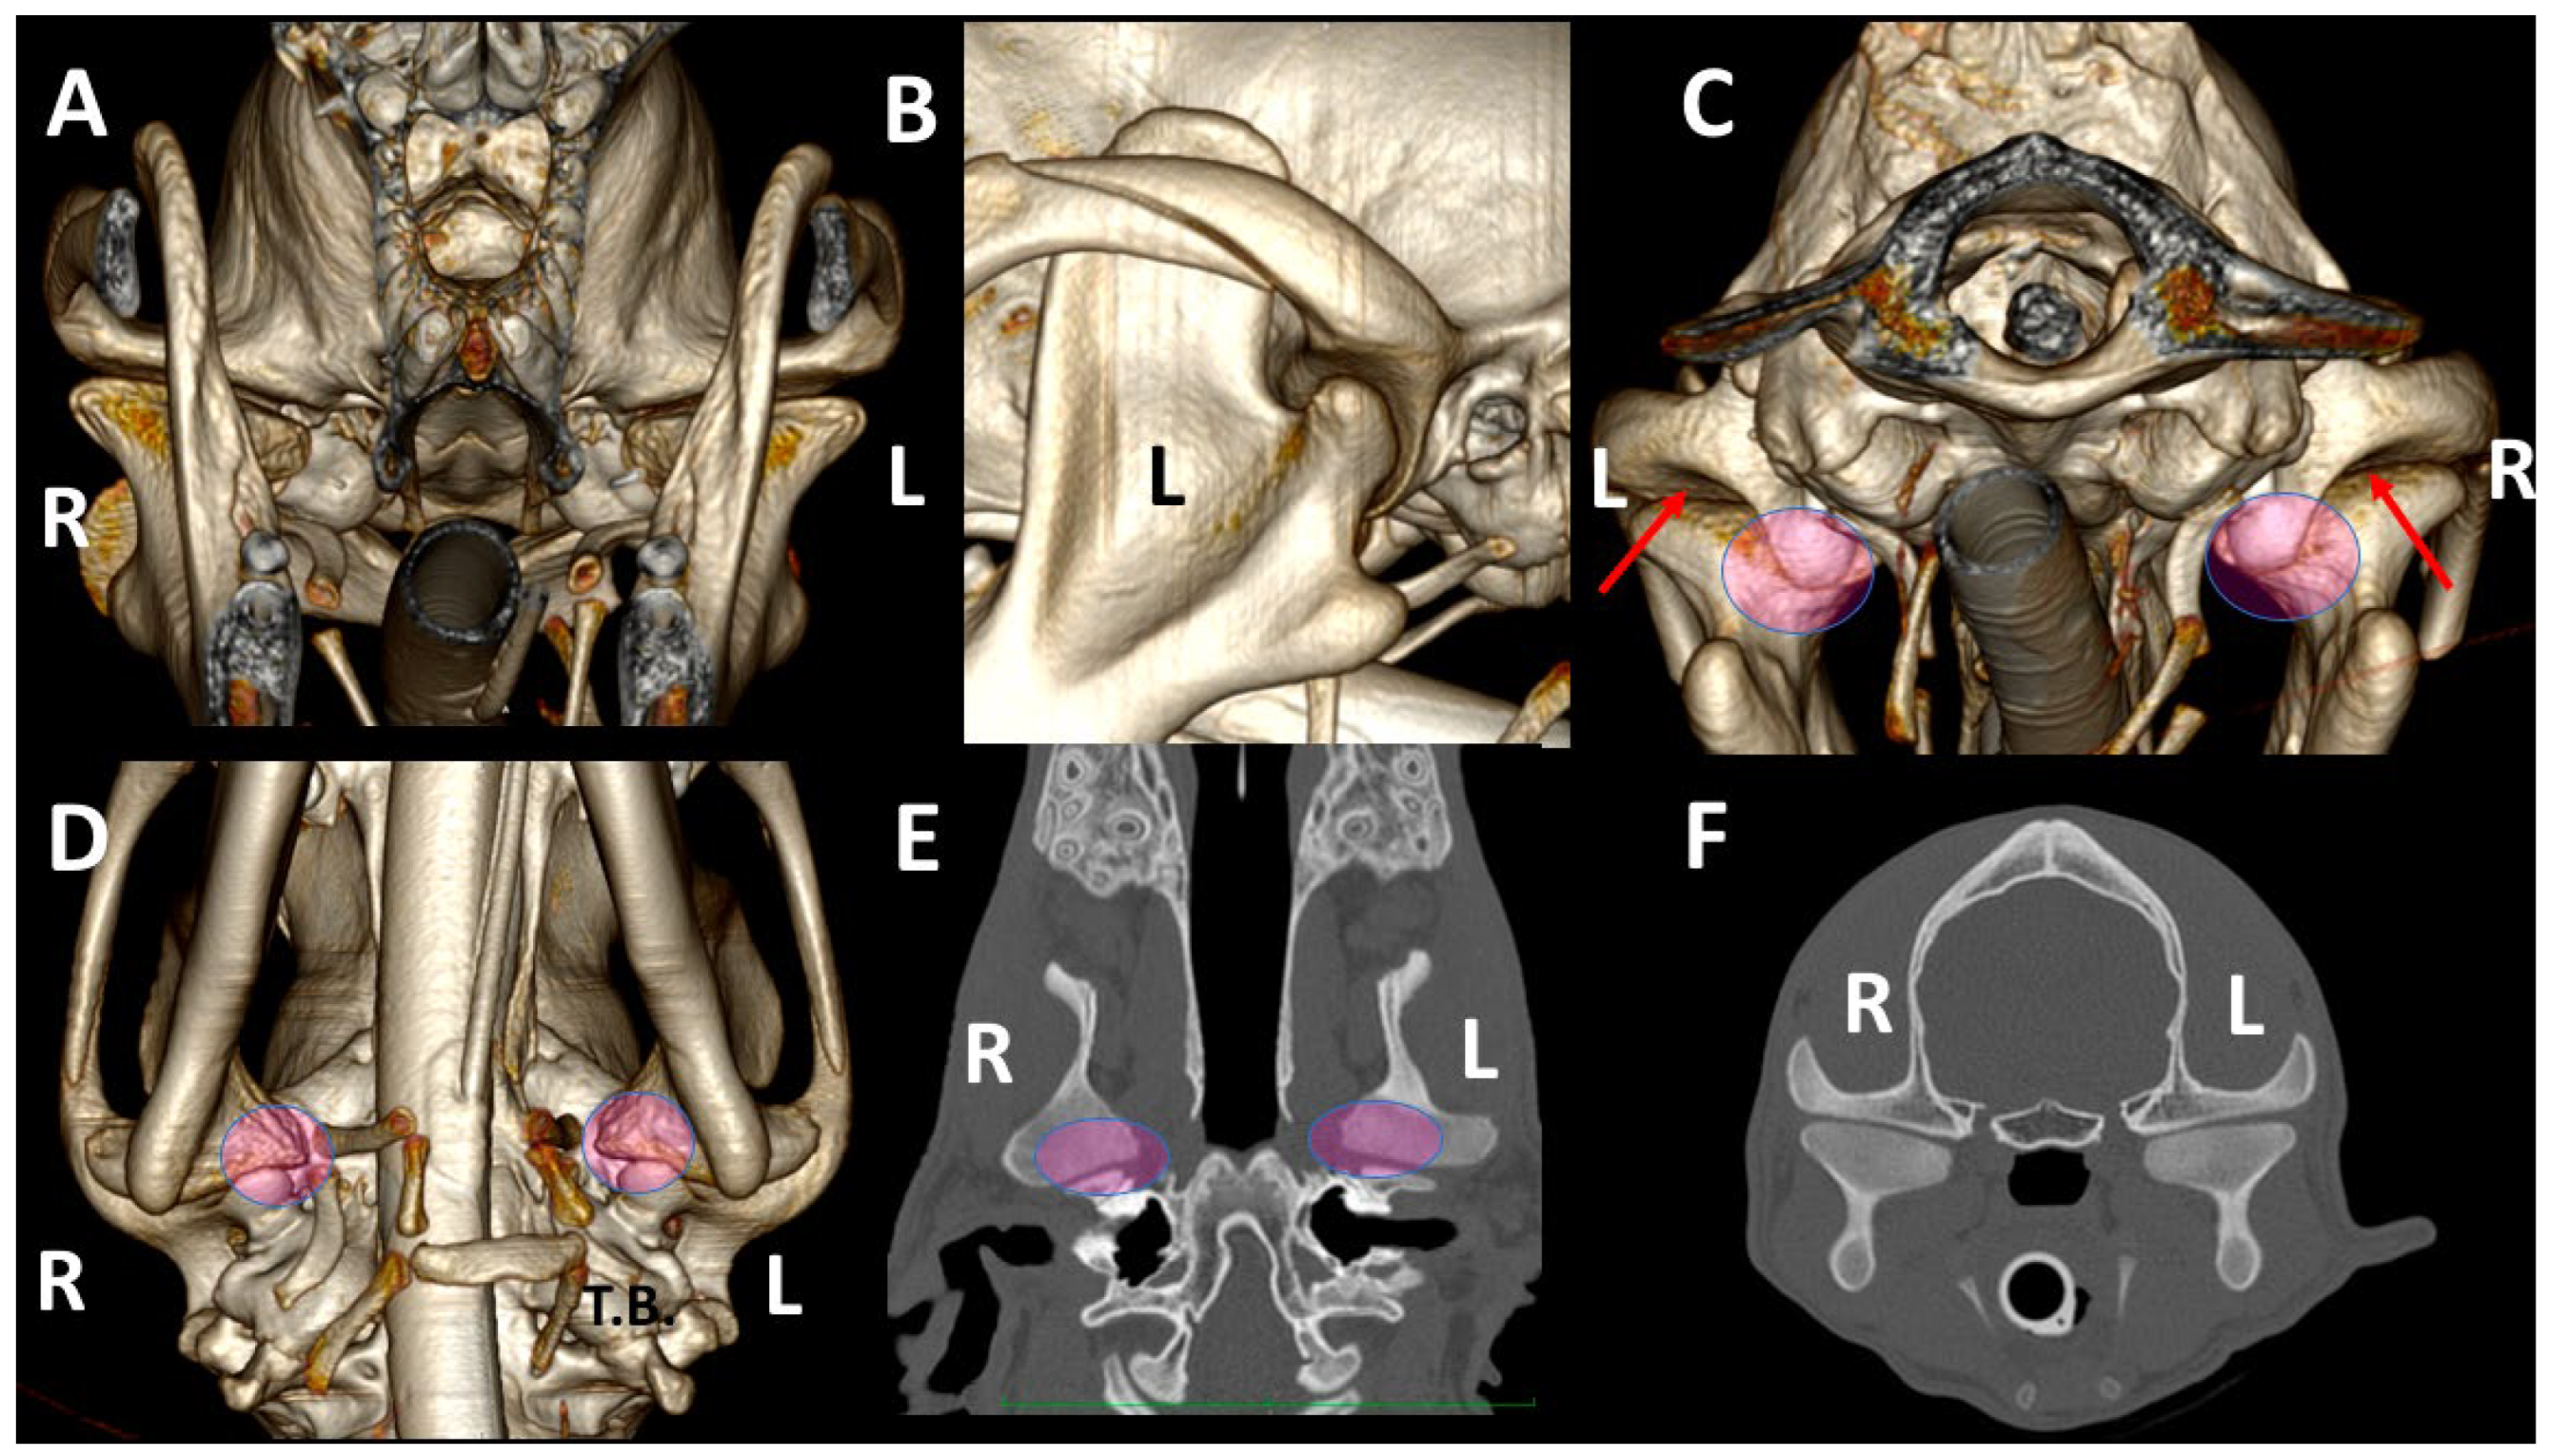

3.3. A Detailed Assessment of Each TMJ Comparing 3DVR Images with the Three Standard CT Planes